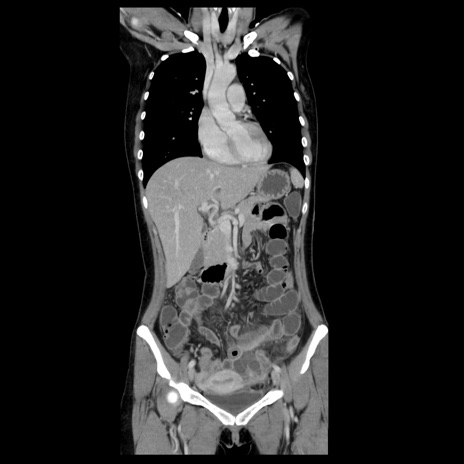

症例39(冠状断像)

【症例】40歳代女性

【主訴】上下腹部痛

【現病歴】2日目から下腹部痛あり。夜間は痛みで眠れなかった。昨日より上腹部痛と下痢が出現。臥位で痛みは軽快したため、休んでいた。本日になって臥位でも立位でも痛みが強くなってきたため救急要請。

【既往歴】子宮内膜症

【身体所見】部:平坦・軟、左上下腹部に圧痛あり、反跳痛あり。

【データ】WBC 21800、CRP 26.78

CT